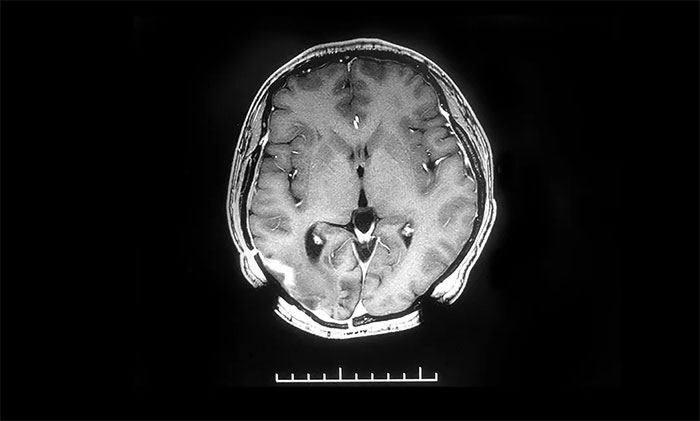

▲治療后

近期,患者來(lái)醫(yī)院復(fù)查,頭顱MR提示原右側(cè)顳枕葉膠質(zhì)瘤術(shù)后改變,較前片病灶明顯縮小。后續(xù)還將根據(jù)患者病情變化,有針對(duì)性地調(diào)整治療,力求延長(zhǎng)患者生存期,提高生存質(zhì)量。